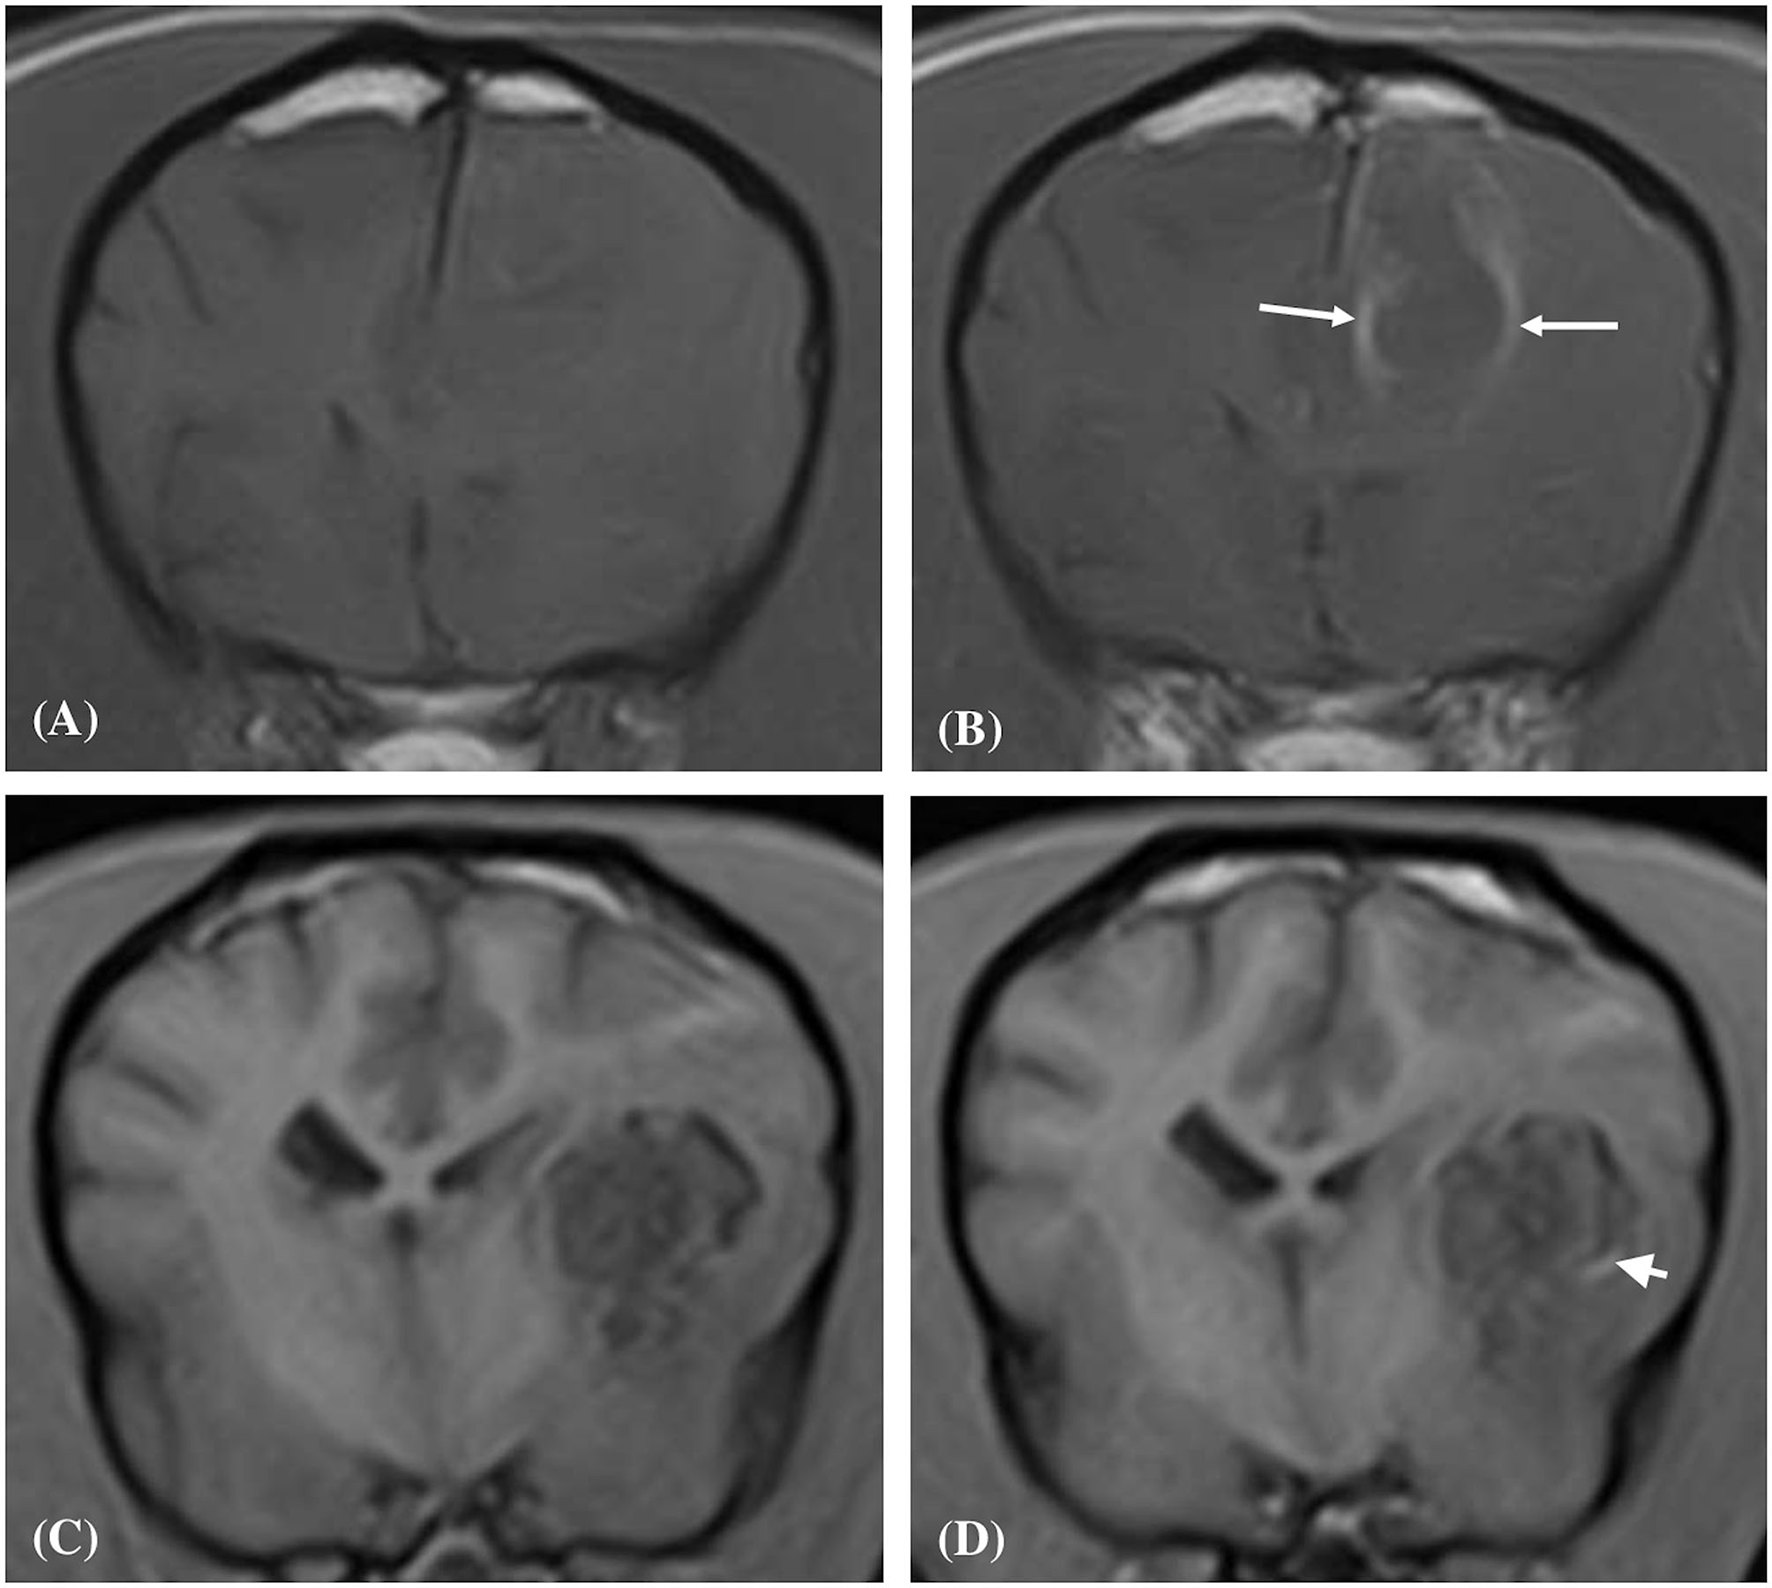

Figure 6

Transverse T2-weighted image (A) of a dog (Case 10) with an intracranial intra-axial hematoma affecting white matter of the left frontal lobe at first presentation. Transverse T2-weighted image (B) of the same dog as displayed in (A) at the same location but 83 days later. Transverse T2-weighted image (C) of a dog (Case 2) with an intracranial intra-axial hematoma affecting the white matter of the left frontal lobe (centrum semiovale) at first presentation. Transverse T2-weighted image (D) of the same dog as displayed in (C) at the same location but 207 days later. In both the follow up images (B,D) the lesions have reduced dramatically in volume, are uniformly hypointense and perilesional oedema has resolved. This is illustrative of normal intra-axial intracranial hematoma contraction and maturation.

Four out of the ten dogs had repeat MRI studies; case 2, case 4, case 8 and case 10 at 207, 32, 46, and 83 days following their initial MRI study, respectively (median value; 64.5 days). On evaluation of these follow-up studies, it was observed that in all four cases the lesions had markedly reduced in volume, were hypointense in all sequences, and both perilesional edema and contrast enhancement were absent (Figure 6).